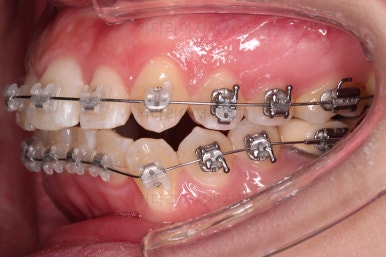

처음 장치를 부착한 사진입니다.

이번에 동래교정치과 선택한 장치는 엠파워 클리어라고 하는 자가결찰 세라믹 장치인데요.

흔히들 클리피씨라고 알고 계신 장치의 종류입니다.

엠파워와 클리피는 제조국만 미국, 일본으로 차이가 나고 큰 틀에서는 같은 장치라고 보시면 됩니다.

동래교정치과 장치 부착 사진인데요.

세라믹이라 비교적 장치가 많이 눈에 띄지 않고요.

입은 장치의 볼륨감으로 약간 튀어나오는 모습입니다.